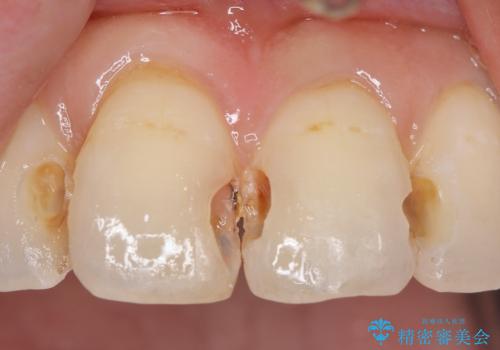

前歯の劣化したコンポジットレジン修復をセラミッククラウンへ

- 数年前に前歯の虫歯治療し、コンポジットレジン修復がなされてい箇所の審美障害の改善を希望され来院されました。

再度レジン修復を行うか、劣化のスピードは遅いが歯の削合が必要なセラミッククラウンの治療の選択肢をご提案し、今後のやりかえの心配の少ないセラミッククラウン治療を希望されました。